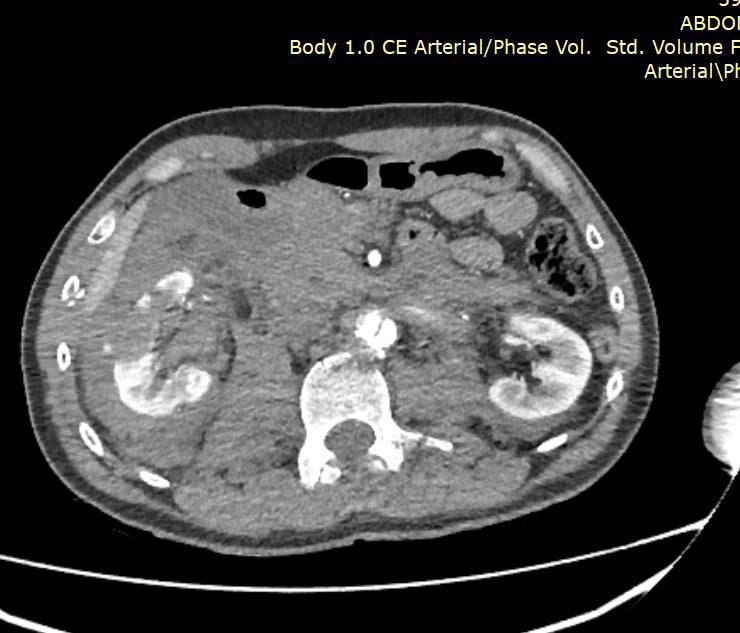

После госпитализации у пациента обнаружили массивную забрюшинную гематому, разрыв инфраренального отдела брюшной аорты, повреждение правой почки и поджелудочной железы.

Чтобы спасти человека, врачи провели экстренную операцию. Во время нее медики удалили почку с правой стороны, зашили разрыв брюшной аорты и перевязали поврежденные поясничные артерии.